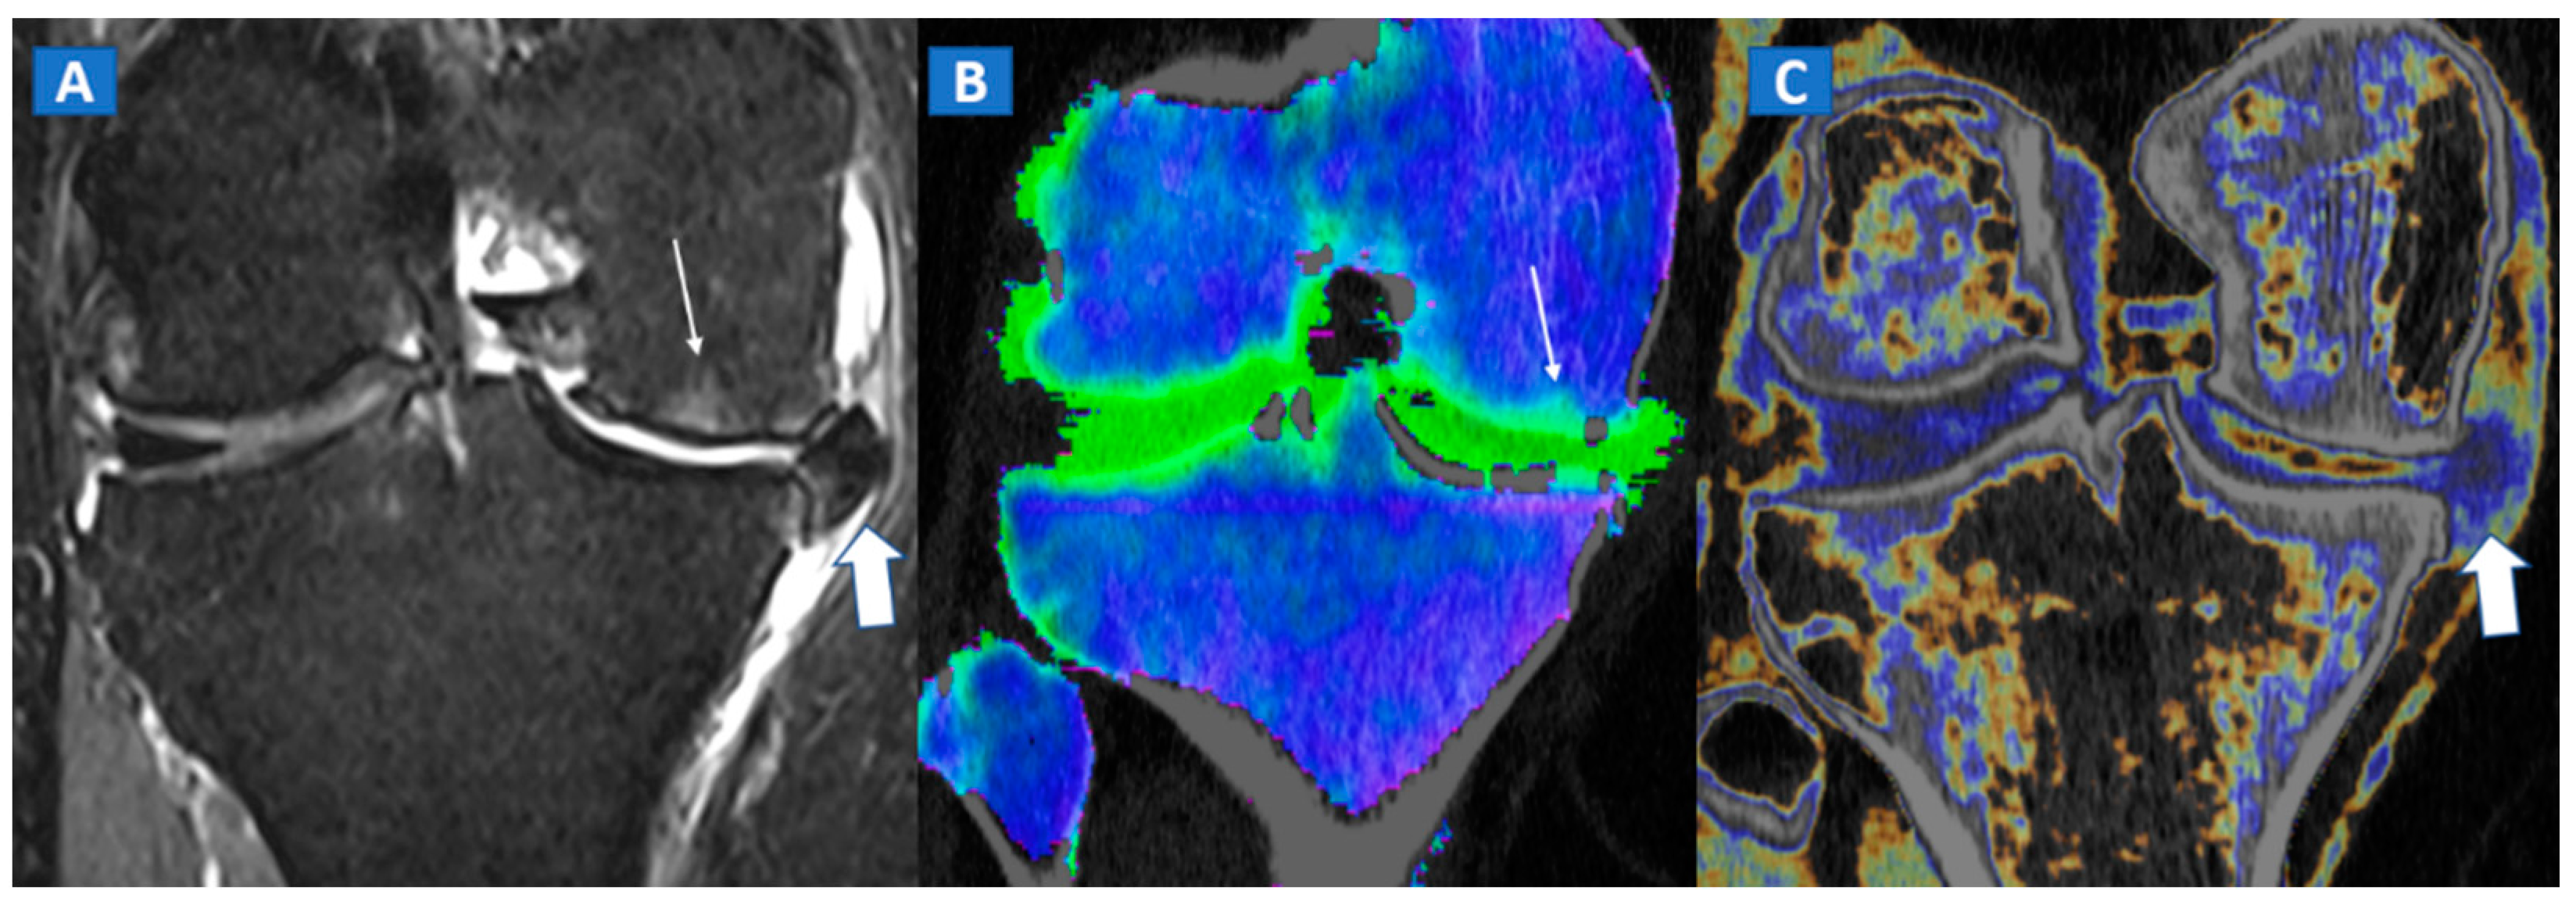

A 65-year-old female with non-traumatic medial-sided knee pain. On the coronal STIR MRI image (A) the body of the medial meniscus is ruptured and medially dislocated (thick arrow). Tiny, subtle BME areas can be seen on the femoral condyle (thin arrow) due to advanced chondropathy. Tiny areas of BME (thin arrow) are also depicted on the corresponding coronal 1 mm reconstructed DECT image (B). By using alternative color-coding (C), DECT allows the depiction of the ruptured meniscus (thick arrow), providing a good correlation with MRI findings.